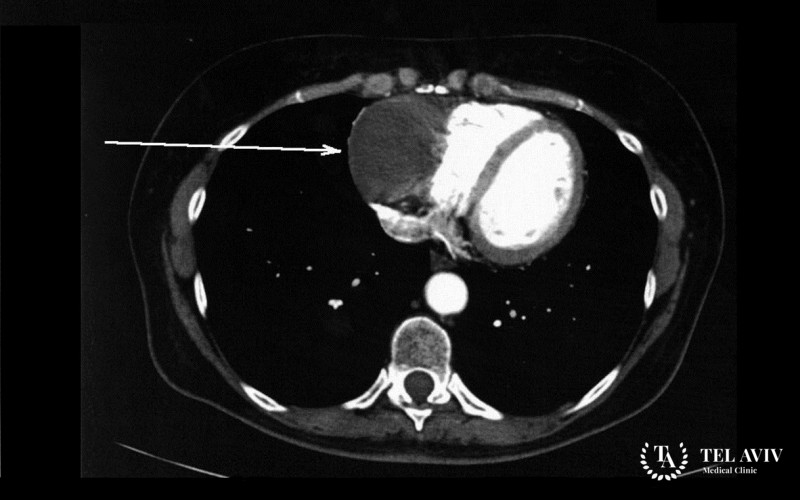

- Визуализация опухоли и близлежащих анатомических структур с помощью КТ и МРТ.